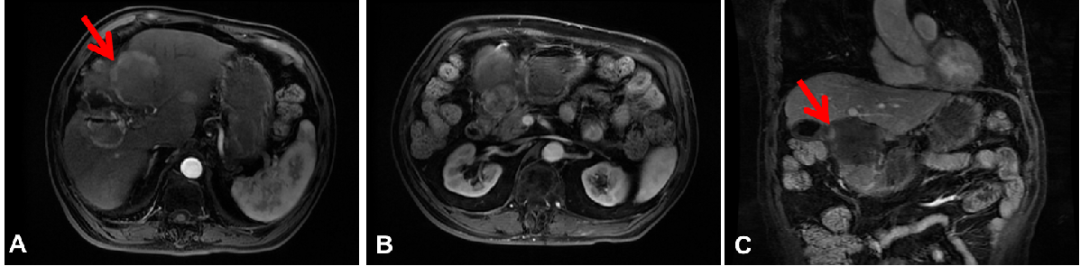

图2:2019年7月3日,第一次介入治疗后腹部CT

患者于2019年7月26日予以第二次TACE治疗,分别于7月30日、9月11日予以放射性粒子植入术。12月12日(第三次介入治疗3个月后)腹部CT提示:存活病灶范围明显增大,肝内新发多发子灶,于2020年1月15日再次予以TACE治疗。

腹部CT:存活病灶范围明显增大,肝内新发多发子灶。

AFP:409.1 ng/ml。

图3:2020年3月13日,第四次介入治疗后腹部CT横断位(A、B)和冠状位(C)